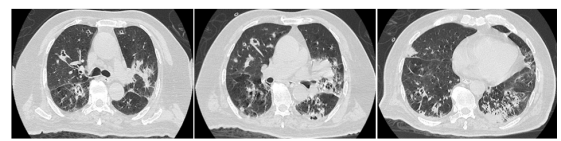

胸部CT检查结果显示“双肺多发炎症伴有空洞形成”,呼吸重症团队立即完善气管镜肺泡灌洗液病原体检查,发现元凶不止一个:军团菌、烟曲霉、甲流同时吞噬着他的双肺(图1:胸部CT)。

图1

这是一场来势汹汹的感染:军团菌导致全身中毒和呼吸衰竭,曲霉菌则喜欢在免疫力低下时“定居”并蚕食肺部形成空洞,而流感病毒则为“潘多拉魔盒的钥匙”——为以上两种病原体敞开大门。